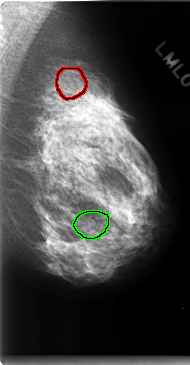

C_0150_1.LEFT_MLO

LEFT_MLO LINES 4736 PIXELS_PER_LINE 2464 BITS_PER_PIXEL 12 RESOLUTION 50 OVERLAY

FILE: C_0150_1.LEFT_MLO.OVERLAY

TOTAL_ABNORMALITIES 2

ABNORMALITY 1

LESION_TYPE CALCIFICATION TYPE AMORPHOUS DISTRIBUTION CLUSTERED

ASSESSMENT 4

SUBTLETY 1

PATHOLOGY BENIGN

ABNORMALITY 2

PATHOLOGY MALIGNANT